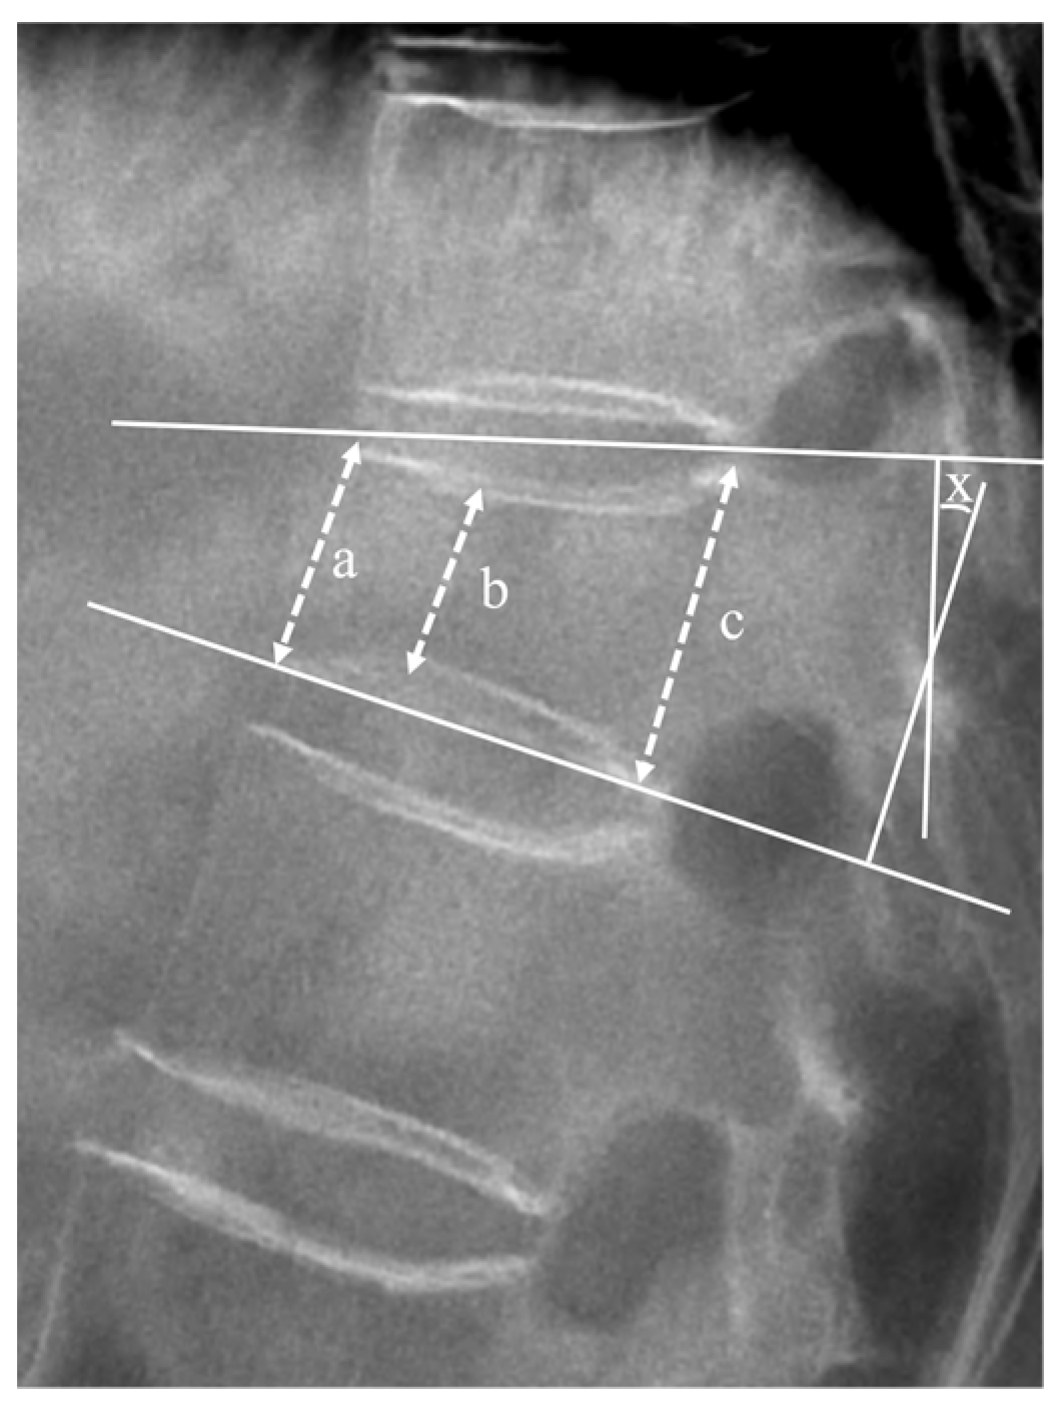

3.4. Radiologic Outcomes

| Vertebral body height ratio, % | |||

| Baseline | 75.65 ± 12.44 | 74.12 ± 19.06 | 0.686 † |

| 6 months | 72.12 ± 12.14 | 70.69 ± 20.51 | 0.438 † |

| 1 year | 70.57 ± 8.63 | 69.85 ± 10.40 | 0.665 † |

| Segmental kyphotic angle, ° | |||

| Baseline | 8.58 ± 4.19 | 8.39 ± 4.47 | 0.907 † |

| 6 months | 6.19 ± 3.35 | 6.20 ± 3.93 | 0.994 † |

| 1 year | 5.59 ± 4.18 | 5.83 ± 4.84 | 0.380 † |